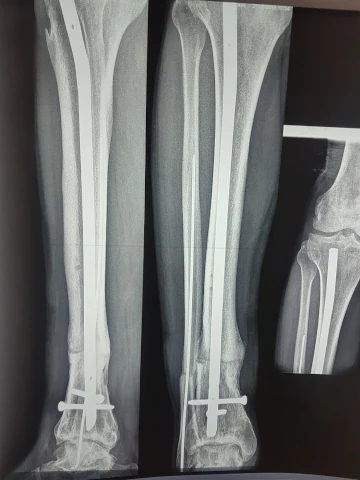

Ostéosynthèse de fracture extracapsulaire du col du fémur

Ostéosynthèse de fracture infratrochantérienne ou trochantérodiaphysaire du fémur

Réduction et fixation de fractures

Réparation de traumatismes musculo-squelettiques